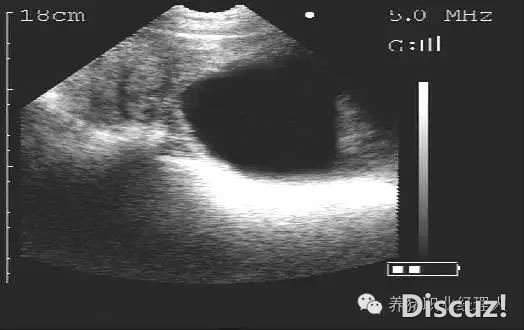

配種母豬不同日齡妊娠B超檢查(圖文并茂,超詳細)

早日發現空懷母豬,減少非生產天數帶來的經濟損失,B超測孕已經成為最普遍的測孕方式。今天,就給大家講解一下B超在現場的使用!正確熟練的使用B超儀,可以準確判斷母豬妊娠情況,減少非妊娠母豬,從而縮短無效飼養 ...